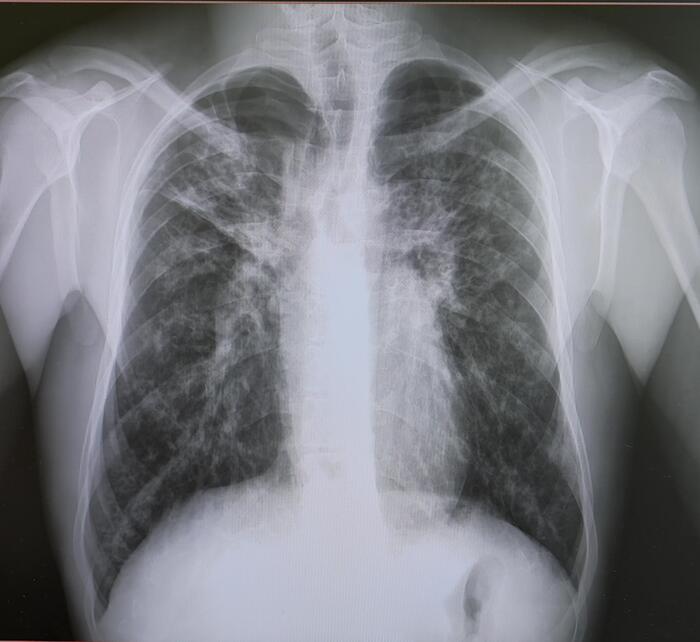

Двустороннее ассиметричное скопление жидкости плотностью +10-20 HU,с максимальной толщиной выпота справа -42мм,слева-16мм(ориентировочный объем жидкости справа-530мл,слева-157мл).

Заключение: Двусторонний гидроторакс, средний по объему-справа, малый-слева.